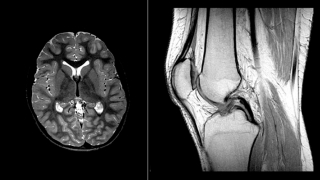

Anatomical Imaging

MRI (Magnetic Resonance Imaging) is a tool now commonly used in hospital and outpatient settings, used to acquire detailed imaging without the use of Ionizing Radiation. Common body parts imaged using MRI include the Brain (Left side of the Left image above) and the Knee (Right side of the Left image above). Curious what certain items look like using MRI? Examples of fruits and vegetables in an MRI environment are represented above (Right image).